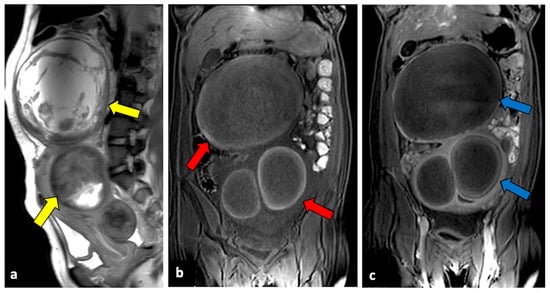

The degeneration or torsion of uterine leiomyomas usually occurs in subserosa and pedunculated fibroids, and it is a rare but potentially life-threatening cause of APP. The severity of symptoms depends mainly on the degree of rotation: if pedicle torsion is partial and spontaneously untwisting, symptoms are usually mild; nevertheless, a complete torsion leads to venous stasis, with oedema and congestion, and then causes compression of the arterial blood supply. Obstruction of the arterial network produces haemorrhagic necrosis. If not treated, massive bleeding or peritonitis may occur [50]. US, CT, and MRI are all imaging tools that are useful for fibroids torsion. The most typical imaging findings are a para-uterine mass with a twisted pedicle, vascular flow absence, and mild free abdominal fluid (Figure 7) [50,51].

Figure 7.

Torsion of a leiomyoma in a 36-year-old woman with acute abdominal and pelvic pain. US (a,b) shows a normal uterus (yellow arrows) surrounded by multiple dilated vessels. In a previous MR (c), a large pedunculated leiomyoma was observed (blue arrows). In a CT scan (d), two pedunculated fibroids are seen; the right one is relatively hypodense, with free fluid in the paracolic gutter (red arrow). Surgery findings confirmed the diagnosis of leiomyoma torsion.